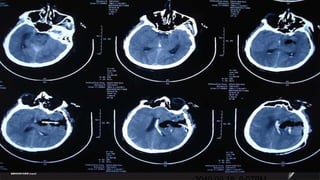

Case  Male ,47ys 2010.09.17  9:17PM Sudden onset of headache and hemiparalysis Muscle strength 0 degree, GCS11 .  BP180/120mmHg

2010.09.18  1:11:17PM

2010.09.18  6:07PM

2010.09.20  2pm

2010.09.25  9AM

2010.09.29  11AM

Case Male,47ys 2010.09.17 9:17PM Sudden onset of headache and hemiparalysis Muscle strength 0 degree, GCS11 . BP180/120mmHg